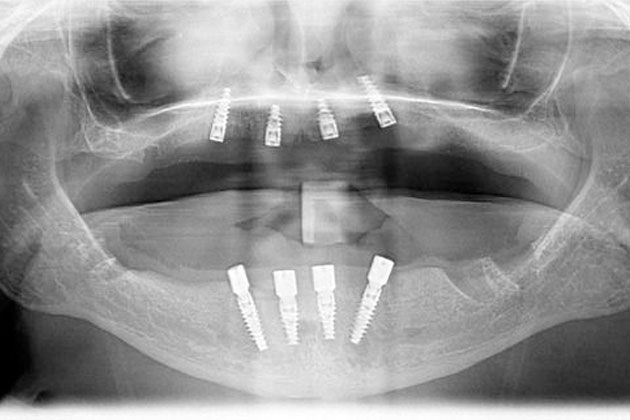

Implant-Supported Crown

A dental implant is a small post that is surgically inserted into the jaw, where it fuses with the bone and functions like the root of a tooth. Once the post has fused with the bone, we will attach a natural-looking and durable dental crown to restore your smile and oral health.